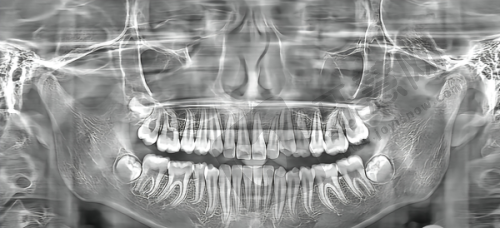

面对韩国uf种植体和奥齿泰种植体,特别多人不知道该如何选择。其实,选择适合自己的种植体需要综合考虑多个因素。首先要考虑自己的经济预算,如果预算有限,韩国uf种植体的价格优势会比较明显,可以优先考虑。

其次,要考虑自己的口腔状况。如果牙槽骨条件较好,对种植体的生物活性和稳定性要求不是特别高,韩国uf种植体也能满足需求。但如果牙槽骨条件较差,或者对种植体的质量和成功几率有较高要求,那么奥齿泰种植体可能更合适。

末尾,建议患者到正规医院详细面诊。专精的医生会根据患者的口腔情况、经济状况等因素,推荐适合患者的种植体品牌和型号,帮助患者获得理想的牙齿修复结果。